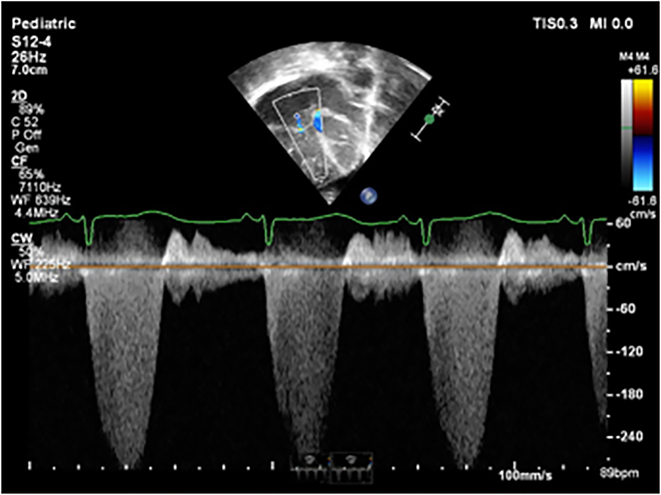

Case presentation: A term infant was diagnosed with severe PPHN with echocardiographic features noted at 6 h after birth which included supra-systemic pulmonary pressures, severe isolated right ventricle (RV) hypertrophy, poor RV dysfunction and no ductal flow in the context of a structurally normal heart. There was maternal use of low-dose aspirin in pregnancy due to preeclampsia. There is a known association between use of prostaglandin synthase inhibitors such as aspirin with ductal closure leading to increased RV pressure. Treatment was commenced with positive pressure ventilation, inhaled nitric oxide (iNO) and milrinone. There was a limited response to iNO necessitating increasing the concentration of milrinone with a marked improvement in oxygenation. Following commencement of sildenafil, inhaled nitric oxide was gradually weaned and stopped in the third week and the infant extubated. The infant was discharged home on oral sildenafil at four weeks of age with no respiratory or feeding support. Echocardiographic features of raised right sided pressures persisted, but with reduced RV hypertrophy and septal flattening and improved RV function. Oral sildenafil was subsequently weaned and stopped at four months of age.